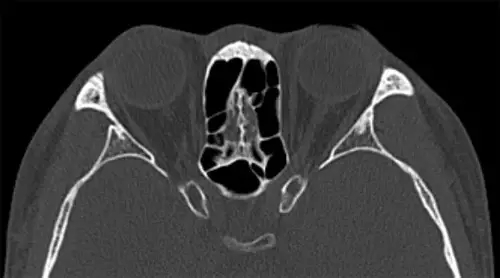

视神经管CT